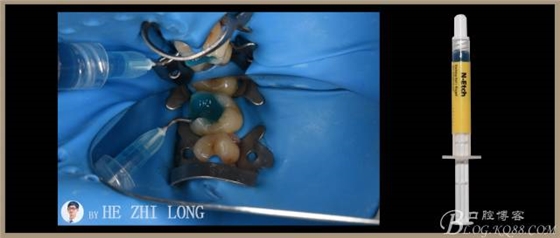

1、橡皮障隔濕,基牙粘結(jié)面噴砂處理或使用不含氟拋光膏清潔。

2、用37%磷酸(N-Etch)酸蝕基牙粘結(jié)面30S(如果是活髓牙,則牙釉質(zhì)酸蝕15-30S,牙本質(zhì)酸蝕10-15S),沖洗,牙釉質(zhì)吹干,牙本質(zhì)保持微濕潤(rùn)。

3、涂牙本質(zhì)處理劑?①液(Syntac Primer),等15S,吹干。

4、涂牙本質(zhì)粘結(jié)劑②?液(Syntac Adhesive),等10S,吹干。

5、涂牙釉質(zhì)粘結(jié)劑③??液(Heliobond),吹均勻,光固化10S。

2、在根管治療和粘結(jié)修復(fù)方面,橡皮障的應(yīng)用為方便牙體手術(shù)操作和確保手術(shù)質(zhì)量做出了重要貢獻(xiàn)。針對(duì)此病例,我想強(qiáng)調(diào)的是,橡皮障夾的喙部與牙頸部應(yīng)有4點(diǎn)接觸,以確保固位穩(wěn)定。此病例在上橡皮障過程中,由于#25橡皮障夾選擇過大,與牙頸部?jī)H有2點(diǎn)接觸,導(dǎo)致橡皮障夾的喙部往頸部下滑,壓迫牙齦,給患者帶來了不適感。